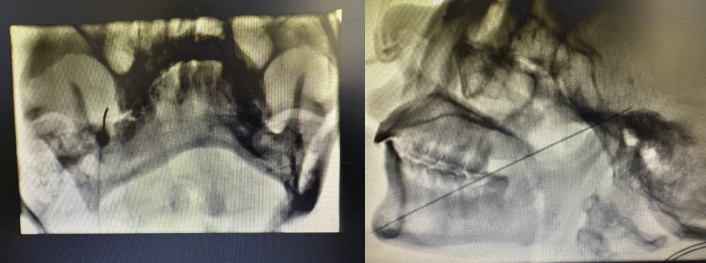

在完善术前评估与准备后,疼痛科团队在介入引导下为患者施行手术。术中仅通过一根细穿刺针进行操作,体表创口微小,并在局部麻醉下完成,患者保持清醒状态,可与医生实时沟通。通过电刺激确认靶点位置,团队精准作用于受累的三叉神经分支。

术后患者疼痛明显缓解,疼痛评分降至0-1分,实现“当天手术、次日出院”的快速康复效果。该技术为因高龄、合并心脑血管疾病、凝血功能障碍或不愿接受开颅手术的三叉神经痛患者,提供了安全、有效且恢复迅速的治疗新途径。